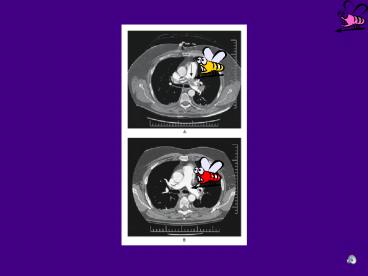

EMBOLIE PULMONAIRESUBMASSIVE

• Confirmation de EP par CT ou angiographie